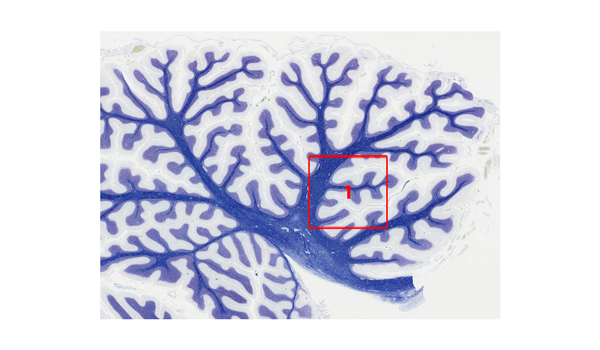

小脳虫部

小脳の矢状断面では、上面から下面の様子を確認することができる。

KB染色

小脳中部正中の矢状断を示している。

小脳皮質・白質